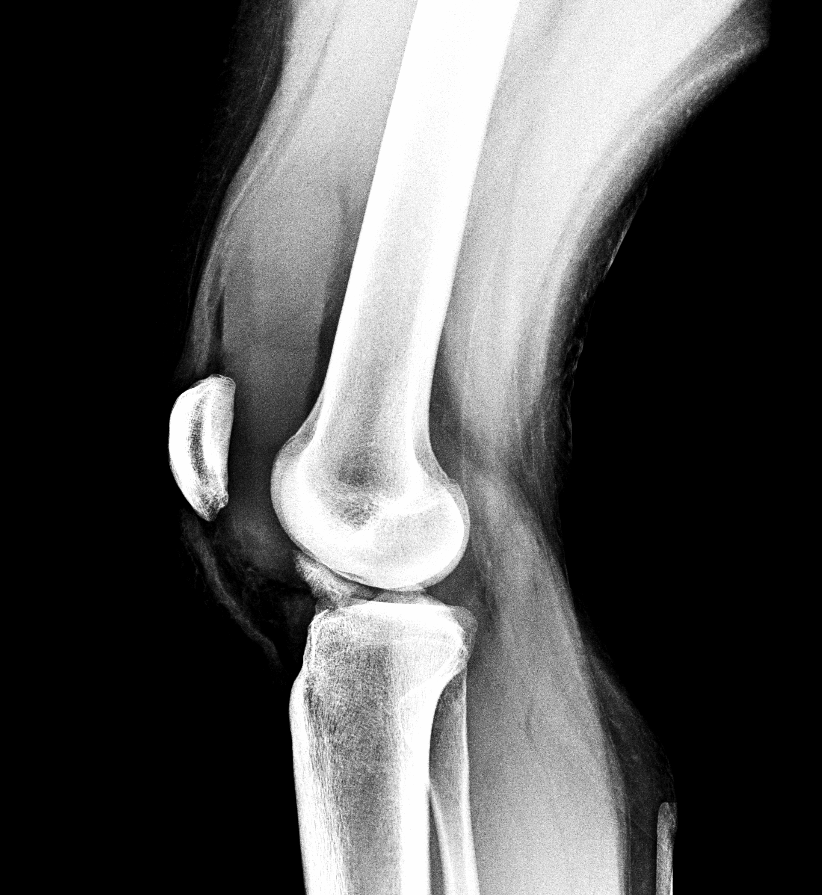

Info Images Findings Impression Reco/Acuity Case Images View Images / Launch Visage Case Notes History 2-month-old presents with decreased right arm movement, increased fussiness, and increased sleepiness for 2 days. Suspected non-accidental trauma. Exam Skeletal survey Prior Study none Dicom View Reference Material

Section 1 Submit Findings CB1550 Findings Skeletal Survey - Technique Check Skull AP/Lat Yes No Cervical and Thoracolumbar spine Yes No Chest X-Ray Yes No Ribs – Left/Right Oblique Yes No Abdominal X-Ray Yes No Pelvis with both hips Yes No Bilateral Humerus, Forearm, Hand Yes No Bilateral Femur, Tibia/fibula, feet Yes No Any additional lateral views of the extremities Yes No The exam is over or under penetrated. Yes No The exam may or may not be limited by overlying structures or soft tissues, body habitus, patient positioning, support devices, or motion. Yes No The area of concern is indicated by the patient, technologist, or care provider. Yes No The area of concern is included on the exam. Yes No Soft Tissues There is soft tissue swelling, indistinctness of fat/muscle planes, gas, or laceration in the area of clinical concern. Yes No There is an effusion, fat pad displacement, or fat fluid level. Yes No There is a radiodense or lucent foreign body. Yes No There are other densities, calcifications, post-surgical changes, or support devices in the soft tissues. Yes No Any support lines/tubes. Yes No Bone There is a break or interruption of the continuity of the cortical or cancellous bone. Yes No There is overriding of the trabeculae with apparent sclerosis. Yes No There is displacement of a fracture fragment. Yes No There is bowing of the bone in addition to the fracture at the apex of the bowed bone concerning for the greenstick. Yes No There is a spiral fracture of the leg concerning for toddler’s fracture. Yes No There is abnormal angulation or bulging of the cortical surface relative to the normal cortex which could be from a buckle or torus fracture. Yes No There is a displaced fragment which may be from avulsion by a tendon, ligament, or joint capsule or from a comminuted or other fracture. Yes No The stress trabeculae or other trabeculae of the cancellous bone are interrupted or otherwise abnormal. Yes No There is subperiosteal or endosteal reaction which could indicate a healing or subacute fracture or other abnormality. Yes No There is hard/soft callus formation. Yes No There is remodeling of the bone. Yes No There is a corner fracture or metaphyseal lesion that could be from nonaccidental trauma. Yes No There are multiple fractures of different ages. Yes No There are vertebral body/spinous process fractures. Yes No There are rib fractures. Location - posterior or lateral. Yes No There is scapular/sternal fracture. Yes No There are fractures of the digits. Yes No There are wormian bones. Yes No There are intrasutural bones. Yes No There is metaphyseal abnormality (lucencies, increased density, erosion) which may be from something other than injury such as stress, metabolic disease (e.g. rickets with loss or distortion of the zone of the provisional calcification), neoplasm (e.g. leukemia), heavy metals, inflammation, or infection. Yes No There are metaphyseal spurs. Yes No There are bony deformities involving multiple bones. Yes No The bones are gracile. Yes No There are non-healing fractures. Yes No There is/are focal or multifocal lytic/lucent, blastic/sclerotic or mixed density lesion(s) or other abnormality. Yes No Overall bone density is increased or decreased with or without thinning or thickening of the cortical or cancellous bone. Yes No Growth plates, ossification centers, apophyses The growth plate(s) is/are abnormal. Yes No There is widening of the physis from a fracture with or without displacement of the epiphysis (Salter-Harris I). Yes No There is a fracture through the physis which then extends into the metaphysis with or without angulation or displacement (S-H II). Yes No There is a fracture through the physis which then extends into the epiphysis and is intra-articular, with or without angulation or displacement (S-H III). Yes No There is a fracture through the metaphysis, physis, and epiphysis which extends into the joint space with or without angulation or displacement (S-H IV). Yes No There is narrowing of the physis from a compression fracture (S-H V). Yes No The apophysis, epicondyle, secondary ossification center, or accessory ossicle is displaced or otherwise abnormal. Yes No The ossification centers are underdeveloped. Yes No Joints and alignment There is an effusion, fat pad displacement, or fat fluid level. Yes No The epiphysis or subchondral bone is fractured, interrupted, flattened, compressed, impacted, displaced, or otherwise abnormal. Yes No There is an intra-articular loose body or chondrocalcinosis. Yes No The joint is widened, narrowed, dislocated, malaligned, or incongruent. Yes No There is pseudoarthrosis. Yes No Other findings There are developmental changes or other anatomic variants or other existing conditions that may or may not be contributing to symptoms which can or should be further evaluated non-emergently or are otherwise incidental. Yes No The remainder of the exam is abnormal for age. Yes No The lungs show focal airspace opacity. Yes No There is pneumothorax. Yes No There is organomegaly. Yes No There is intra-abdominal calcification. Yes No There is displacement of the bowel loops. Yes No There is free intraperitoneal air. Yes No The bowel loops are dilated/obstructed. Yes No There is paraspinal soft tissue abnormality. Yes No